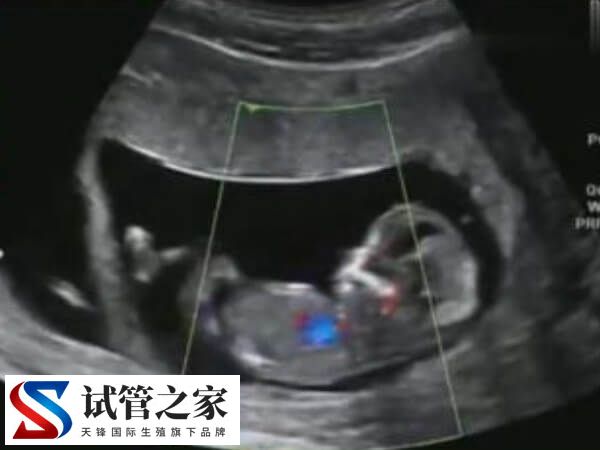

试管婴儿移植成功后,女性需要定期去医院接受孕产检查。这些检查包括血液化验、超声波检查等,以确保宝宝的健康发育和母亲的身体状况。此外在孕期中要遵循医生的建议进行适当的锻炼。